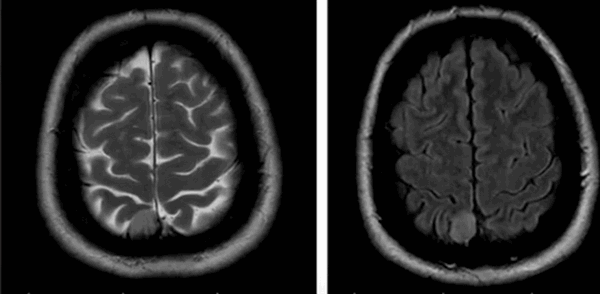

Множественные метастазы в вещество головного мозга на МРТ без контраста

До- и постконтрастное изображение злокачественной опухоли головного мозга

С помощью МРТ при раке мозга выявляют локализацию опухоли, степень ее инвазии в соседние структуры, особенности кровоснабжения, стадию заболевания и наличие метастазов. Для получения дополнительных сведений, сканирование проводят в различных последовательностях (Т1, Т2, FLAIR, диффузно-взвешенное и пр.), в нативном режиме и после контрастирования.